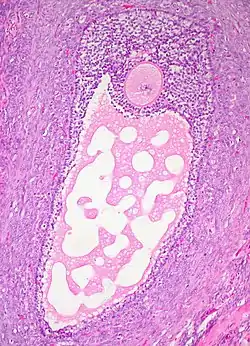

Histology section of a mature ovarian follicle. The oocyte is the large, round, pink-staining cell at top center of the image.

Ovarian follicles are the basic units of female reproductive biology. Each of them contains a single oocyte (immature ovum or egg cell). These structures are periodically initiated to grow and develop, culminating in ovulation of usually a single competent oocyte in humans.[5] They also consist of granulosa cells and theca of follicle.

Once a month, one of the ovaries releases a mature egg (ovum), known as an oocyte. The nucleus of such an oocyte is called a germinal vesicle[6] (see picture).